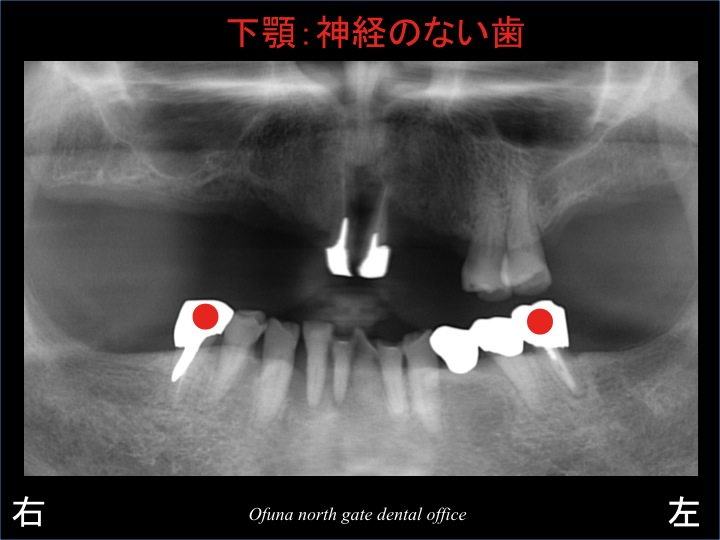

下顎の一番奥の歯は、神経がない歯なのです。

神経のない歯は非常に脆く、歯根破折 のリスクが高い歯です。

神経がない歯の歯根破折 については、このブログを何回か見られている方であればお分かりのことと思います。

ブリッジの土台となる歯が神経がない!

欠損数が多いので、土台には負担が加わりやすい!

等の問題を抱えることになります。

下顎の臼歯部の欠損部で噛めるようにするために、左右の奥歯に1本づつの合計2本のインプラントを埋入することになりました。